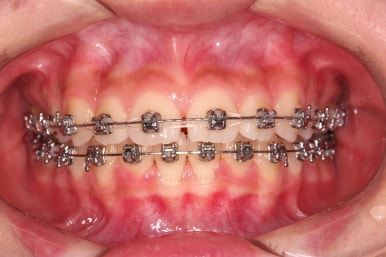

1. 초진 시 입안의 모습 평가

부산치아교정치과 키다리아저씨치과에 처음 내원했을 당시의 입 안의 모습입니다.

전반적으로 윗니가 나와있는 양상이고요.

앞니는 뻐드러져 있네요.

아래 앞니는 위로 솟구쳐 올라서 윗니 뒤쪽을 강하게 치고 있는 과개교합 양상이었고요.

위아래 앞니쪽이 삐뚤어져 있는 상태였습니다.

위아래 치열이 매우 고르게 되었으며, 이제부터는 발치공간을 줄여나가면서 교합을 맞춰 나가면 됩니다.

가지런하게 잘 정렬이 되었고요.

윗니만 발치한 편악발치교정이지만 틈새 없이 공간이 닫혔으며 교합도 잘 맞습니다.

위아랫니가 가지런하게 보기 좋게 배열이 되었고요.

아랫니까지 윗니를 넣음으로써 튀어나와 보이던 앞니의 느낌이 좋아졌습니다.